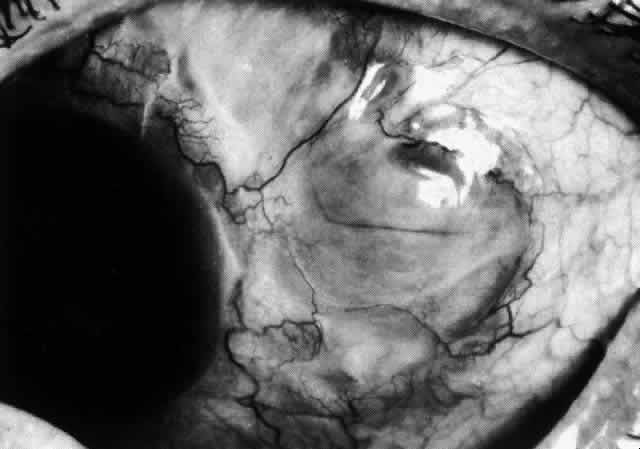

The characteristic features of necrotizing scleritis on fluorescein angiography are hypoperfusion and, eventually, nonperfusion of the vascular networks (Figs. 40 through 43).26 The initial changes are on the venous side of the capillary network; the transit time of the dye increases even if the eye is red and congested. If the disease process persists or has been present for a long time, thrombosis and permanent vaso-occlusive changes occur. These vessels (or the occluded capillary network) are bypassed by the opening of anastomotic channels. New vessels in a granuloma give rise to deep intrascleral leakage of dye (see Fig. 43). Conjunctival and episcleral involvement by the destructive change is late but is always preceded by vaso-occlusive changes that can sometimes be detected with use of the red-free light on the slit lamp (Figs. 44 and 45).

Fig. 40. Early necrotizing scleritis. There is characteristic yellow discoloration of the sclera underlying the conjunctiva at a point of necrosis. In this instance a small filament of tissue has penetrated the conjunctiva.

Fig. 41. Late stage of fluorescein angiogram adjacent to the site of necrosis in the same patient as in Figure 40. Although the eye is uniformly congested, the area near the necrosis shows vascular shutdown, whereas the rest of the conjunctiva and episclera is normally perfused.